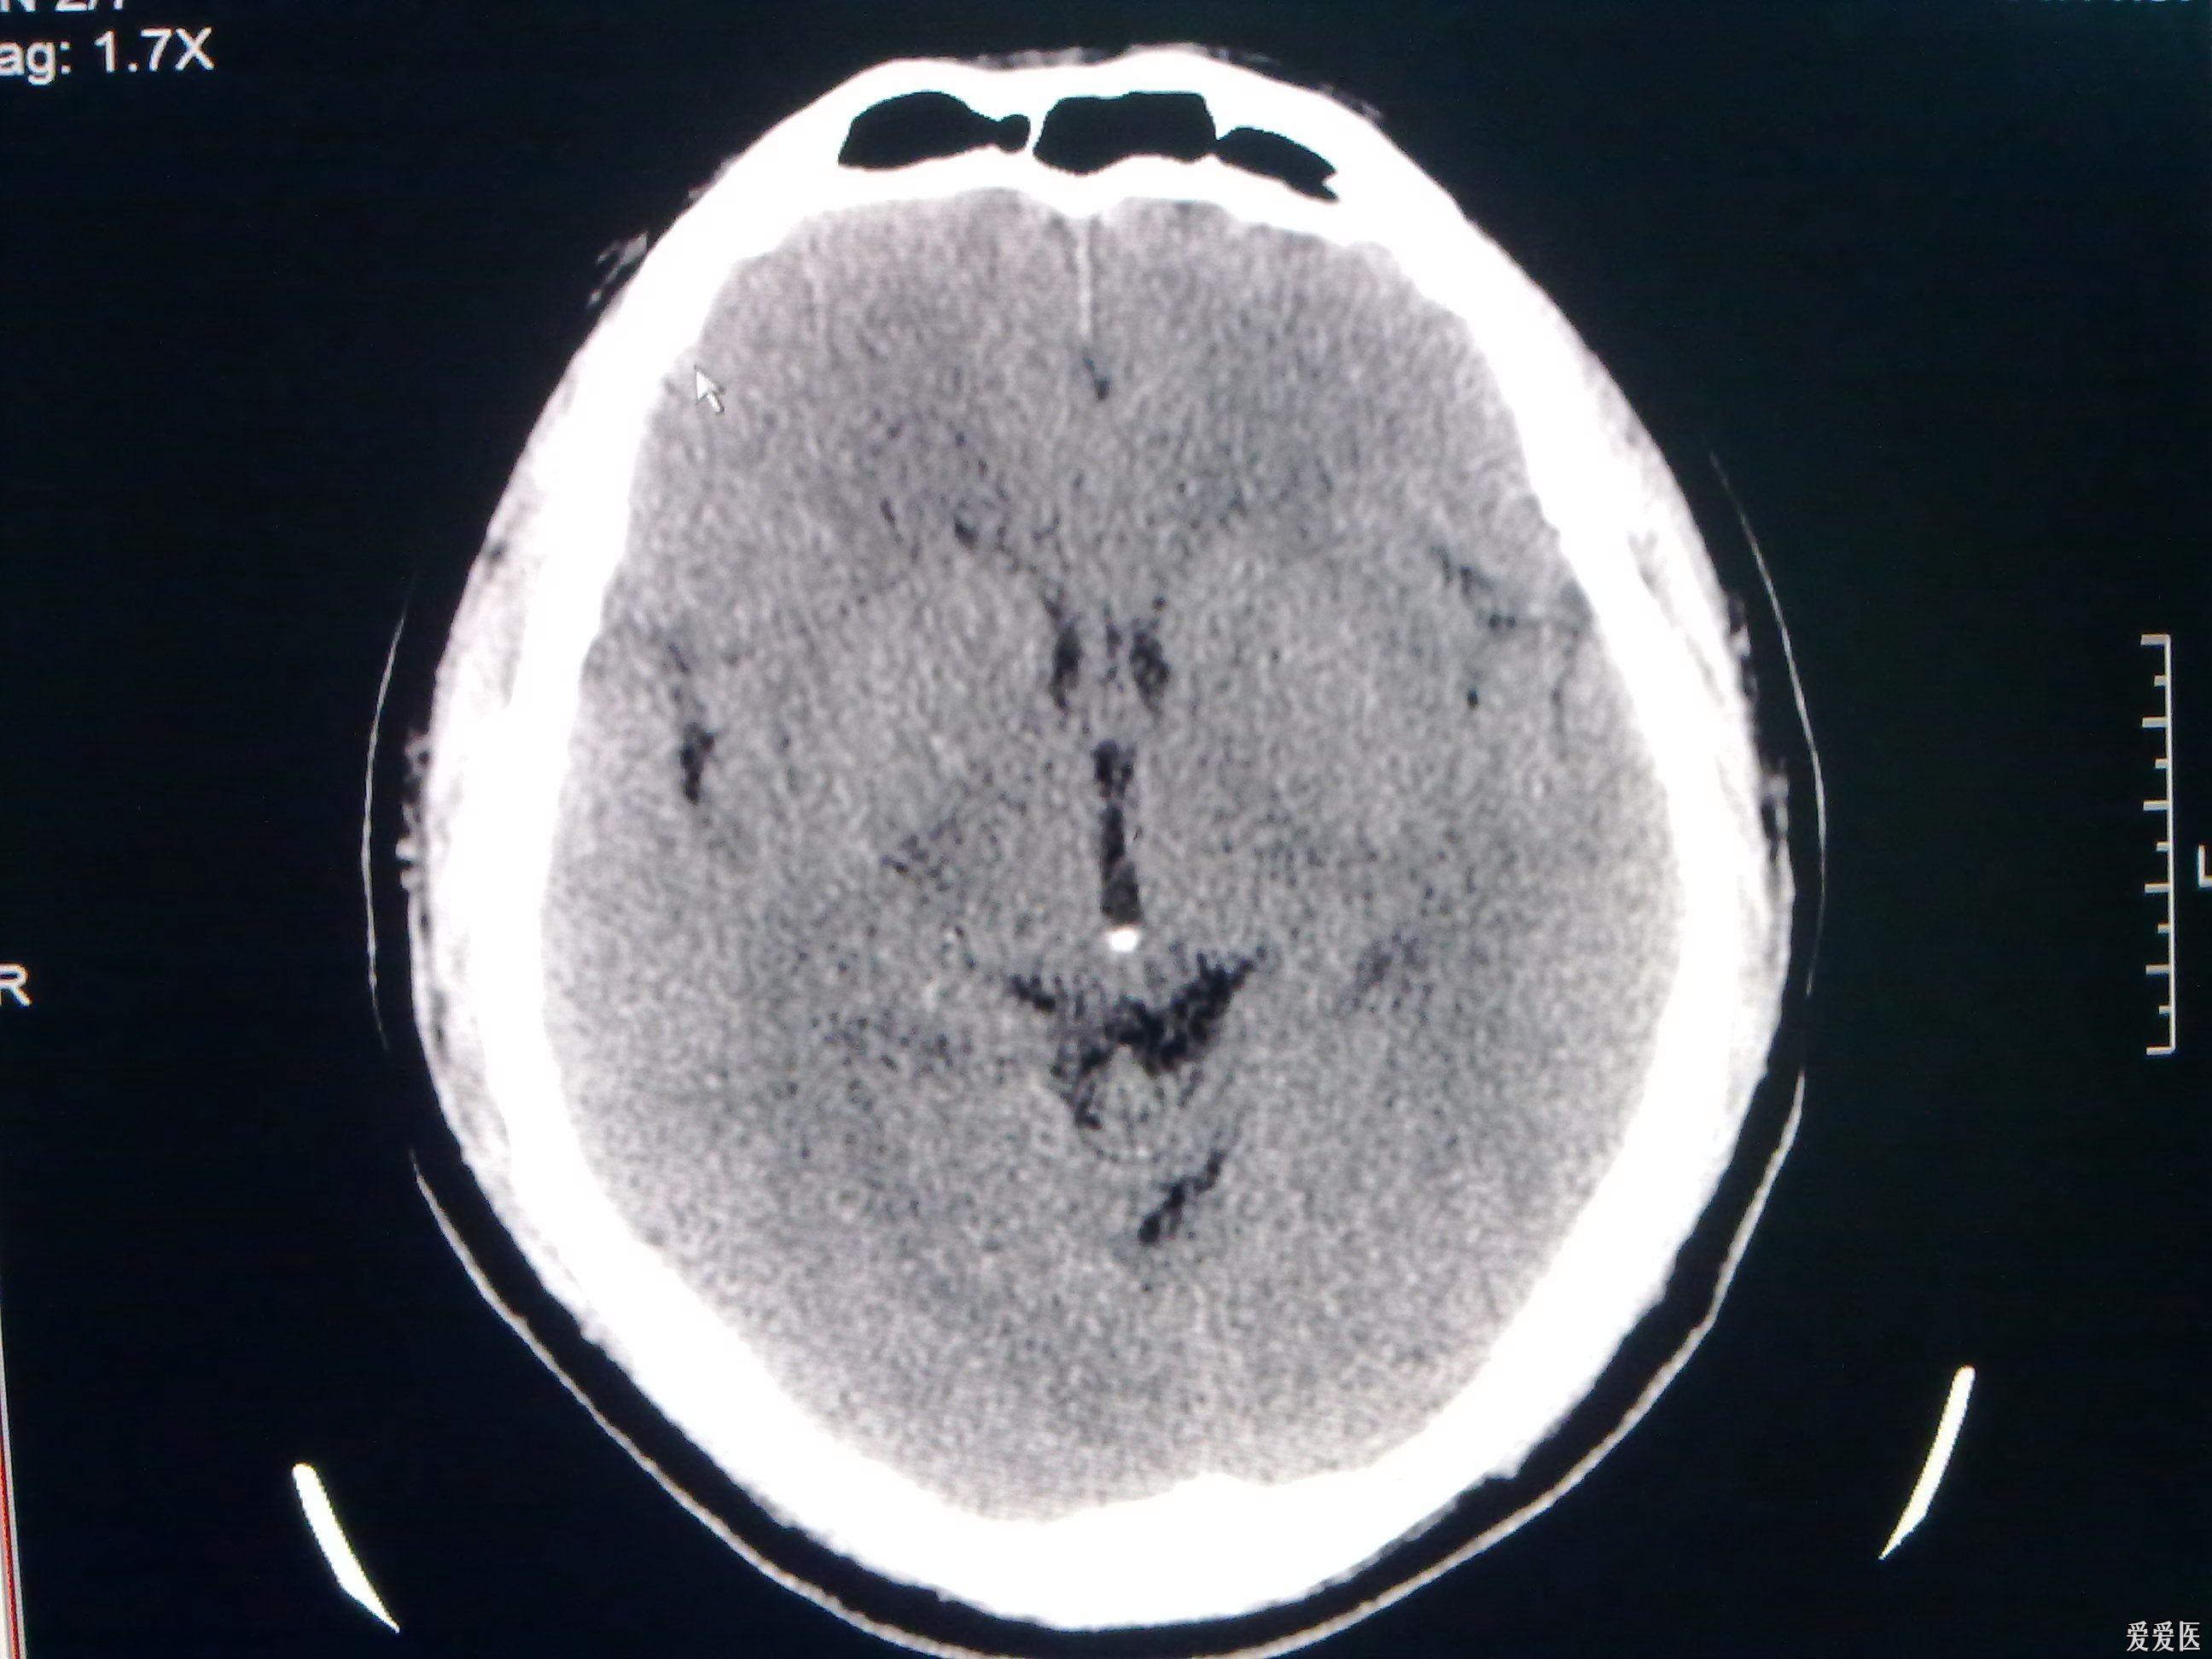

今天做到的病例脑裂畸形

图片尺寸2592x1944

今天做到的病例脑裂畸形

图片尺寸2592x1944

今天做到的病例脑裂畸形

图片尺寸2592x1944

今天做到的病例脑裂畸形

图片尺寸2592x1944